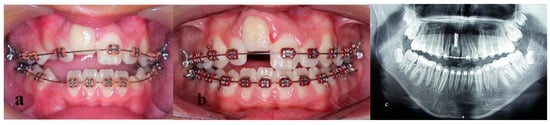

Treatment of an Avulsed and Ankylosed Incisor through Single Tooth Alveolar Osteotomy and Conventional Orthodontic Mechanisms

2. Materials and Methods

3. Results